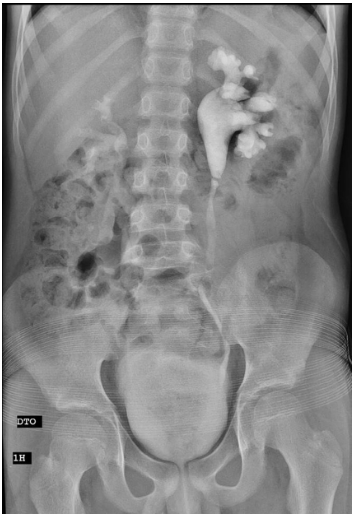

- Radiografia Simples (Plano Simple/Scout): Essencial para avaliar preparo e identificar cálculos radiopacos (90% dos casos). É a base de comparação.

- Fase Nefrográfica (Imediata - ~15-30s pós-injeção): Mostra a opacificação do parênquima renal. Avalia tamanho, contorno e simetria funcional.

A interpretação deve ser sistemática, comparando cada fase com a anatomia normal e com a radiografia simples inicial.

- Contornos Renais: Lisos, com tamanho de 3-4 vértebras.

- Nefrograma: Simétrico e homogêneo.